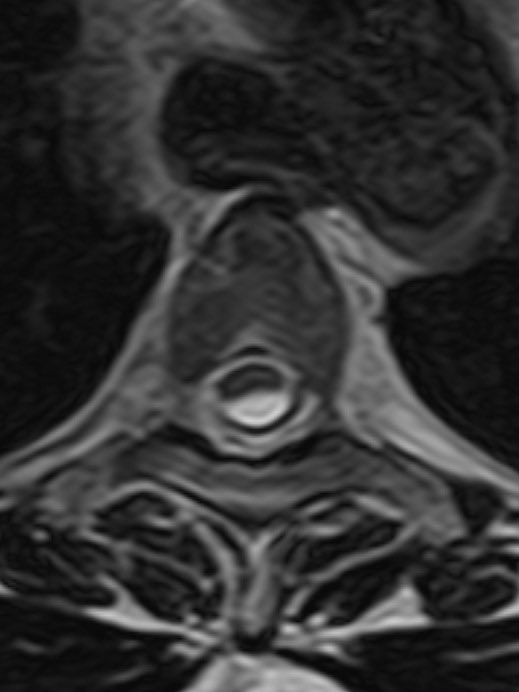

⭐️ Classic case: 60 y/o F presents w/ 3 years progressive pain in legs, difficulty with walking and balance, and occasional overflow incontinence. What is your diagnosis? #MedEd #medicine #Neurology #futureradres #radres #Neurosurgery #MRI @TheASNR #FOAMed

⭐️ Answer: Ventral cord herniation 🔷PATH: Acquired or congenital defect in the ventral dura allows the subarachnoid space and therefore the cord to slip through the defect into the epidural space

🔷IMAGING: ▶️Morphology of the cord at the herniation is focally kinked (rather than the scalpel sign seen in a dorsal thoracic arachnoid web) ▶️No CSF between ventral cord and dura (find this one tough because it can look like this with webs too) ▶️ “Nuclear trail” sign

🔷DIFFERENTIAL: 1️⃣Dorsal thoracic arachnoid web: “Scalpel sign” rather than focal distortion/kinked appearance, may see CSF between cord and dura, may see band like interruption of CSF pulsation artifact at the level of the web (example in 🧵) 2️⃣Arachnoid cyst: Smooth